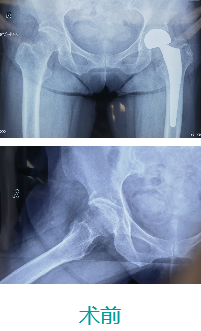

天玑II 辅助股骨颈骨折复位内牢靠术

基本情形:患者男,,,,,,73岁,,,,,,股骨颈骨折

病例泉源:北京积水潭医院